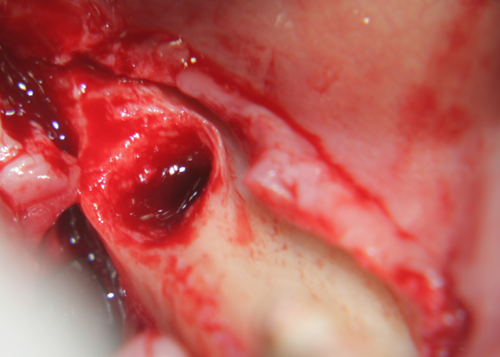

Меките тъкани са отпрепарирани и зъбът е екстрахиран. Вижда се

обширен костен дефект - почти няма стени, само обширно

хлътване. На мястото на апекса на зъба се вижда остатък от алвеола